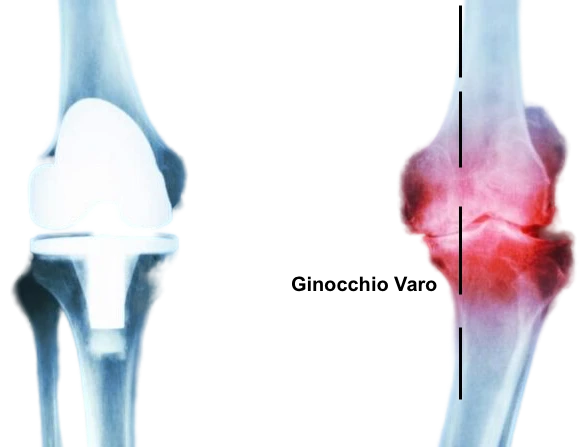

Varismo (gambe a “O”): accentua il sovraccarico del compartimento mediale, aumentando il rischio di artrosi interna.

In condizioni normali l’asse meccanico di carico dell’arto inferiore passa per il centro del ginocchio, le forze di carico sono quindi distribuite uniformemente su tutta l’articolazione. Nel caso del ginocchio varo, il comparto interno del ginocchio viene ad essere sovraccaricato, causandone la progressiva usura. Nel ginocchio valgo, è il comparto esterno ad essere maggiormente sollecitato dalle forze di carico

Il ginocchio varo o valgo provoca una distribuzione asimmetrica del carico sull’articolazione, causando una maggiore usura di una sola porzione della cartilagine. Questo può tradursi in dolore, rigidità e limitazione dei movimenti.

Osteotomia tibiale

Utilizzata principalmente per correggere il ginocchio varo, prevede una incisione sulla faccia mediale della tibia prossimale, il taglio e il rimodellamento dell’osso, seguito da correzione dell’asse e fissazione con placca dedicata.